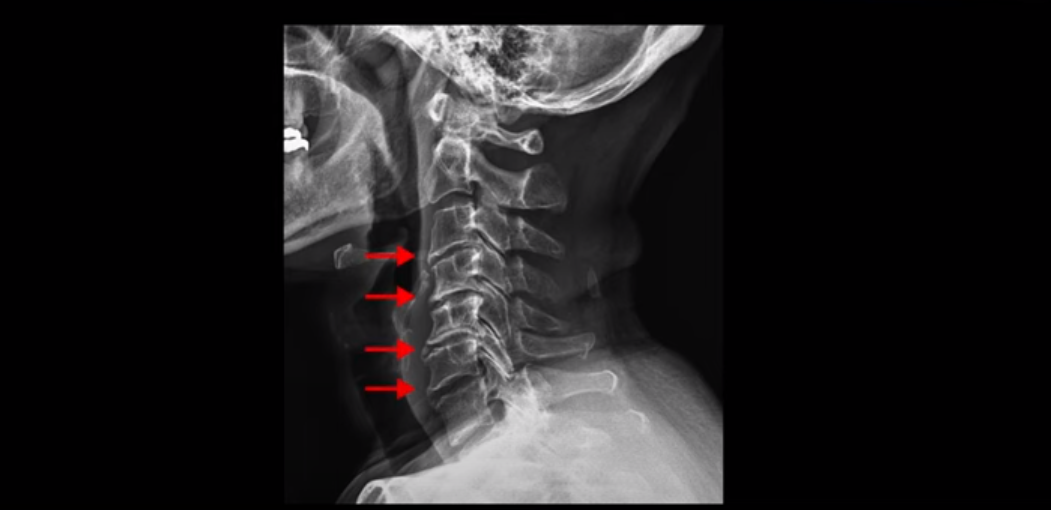

이 환자분 X-ray, MRI 보고 간단히 설명 드린 후 왜 목디스크 치료가 허리디스크에 비해 훨씬 더 쉬운지 자세히 설명 드리겠습니다.

X-ray 보시다시피 완전 일자목 거북목에다 여러 마디가 전부 다 퇴행이 심하며

뼈 모양의 변형도 매우 심합니다.

X-ray로 봐도 신경 구멍들이 좁아진 게 보입니다.

이런 걸 협착이라고 부르는 거죠. 이 분의 가장 불편한 증상은 20년간 아픈 만성적인 목통증과 어깨통증, 두통과 눈 통증인데 최근 들어 가증 불편한 증상은 목이 아예 돌아가지 않는 겁니다. 그래서 운전할 때도 사이드 미러를 보려면 몸을 돌리셨다고 하는데요. 주사 효과도 전혀 없고 대학병원에서도 디스크와 협착인데 그냥 약먹고 운동만 하라고 하면 이 환자는 어떻게 해야 할까요?

이 환자분도 아까 X-ray에서 보여드렸듯이 아주 심한 일자목, 거북목이 있고 그 결과로 목의 거의 모든 마디가 다 퇴행이 진행되어 있죠. 즉 거북목은 모든 목질환, 특히 목디스크, 목협착증의 어머니 질환이며 그래서 목디스크를 치료하기 위해서는 반드시 거북목 때문에 짧아지고 뭉치고 굳고 뒤틀린 목 주변 근육들을 잘 치료해줘야 합니다.